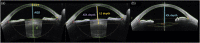

Methods: 423 eyes (423 patients) implanted with a single-piece, L-loop, acrylic IOL were enrolled. All biometric data for the O formula were obtained by anterior segment swept-source optical coherence tomography (SS-OCT) and SS-OCT-based biometer. The performance of the O formula was compared with those of the Barrett Universal II (BUII) and Kane formulas at 1 month postoperatively. Statistical analysis was applied according to a heteroscedastic test with SD of prediction errors as the main parameter for formula performance.